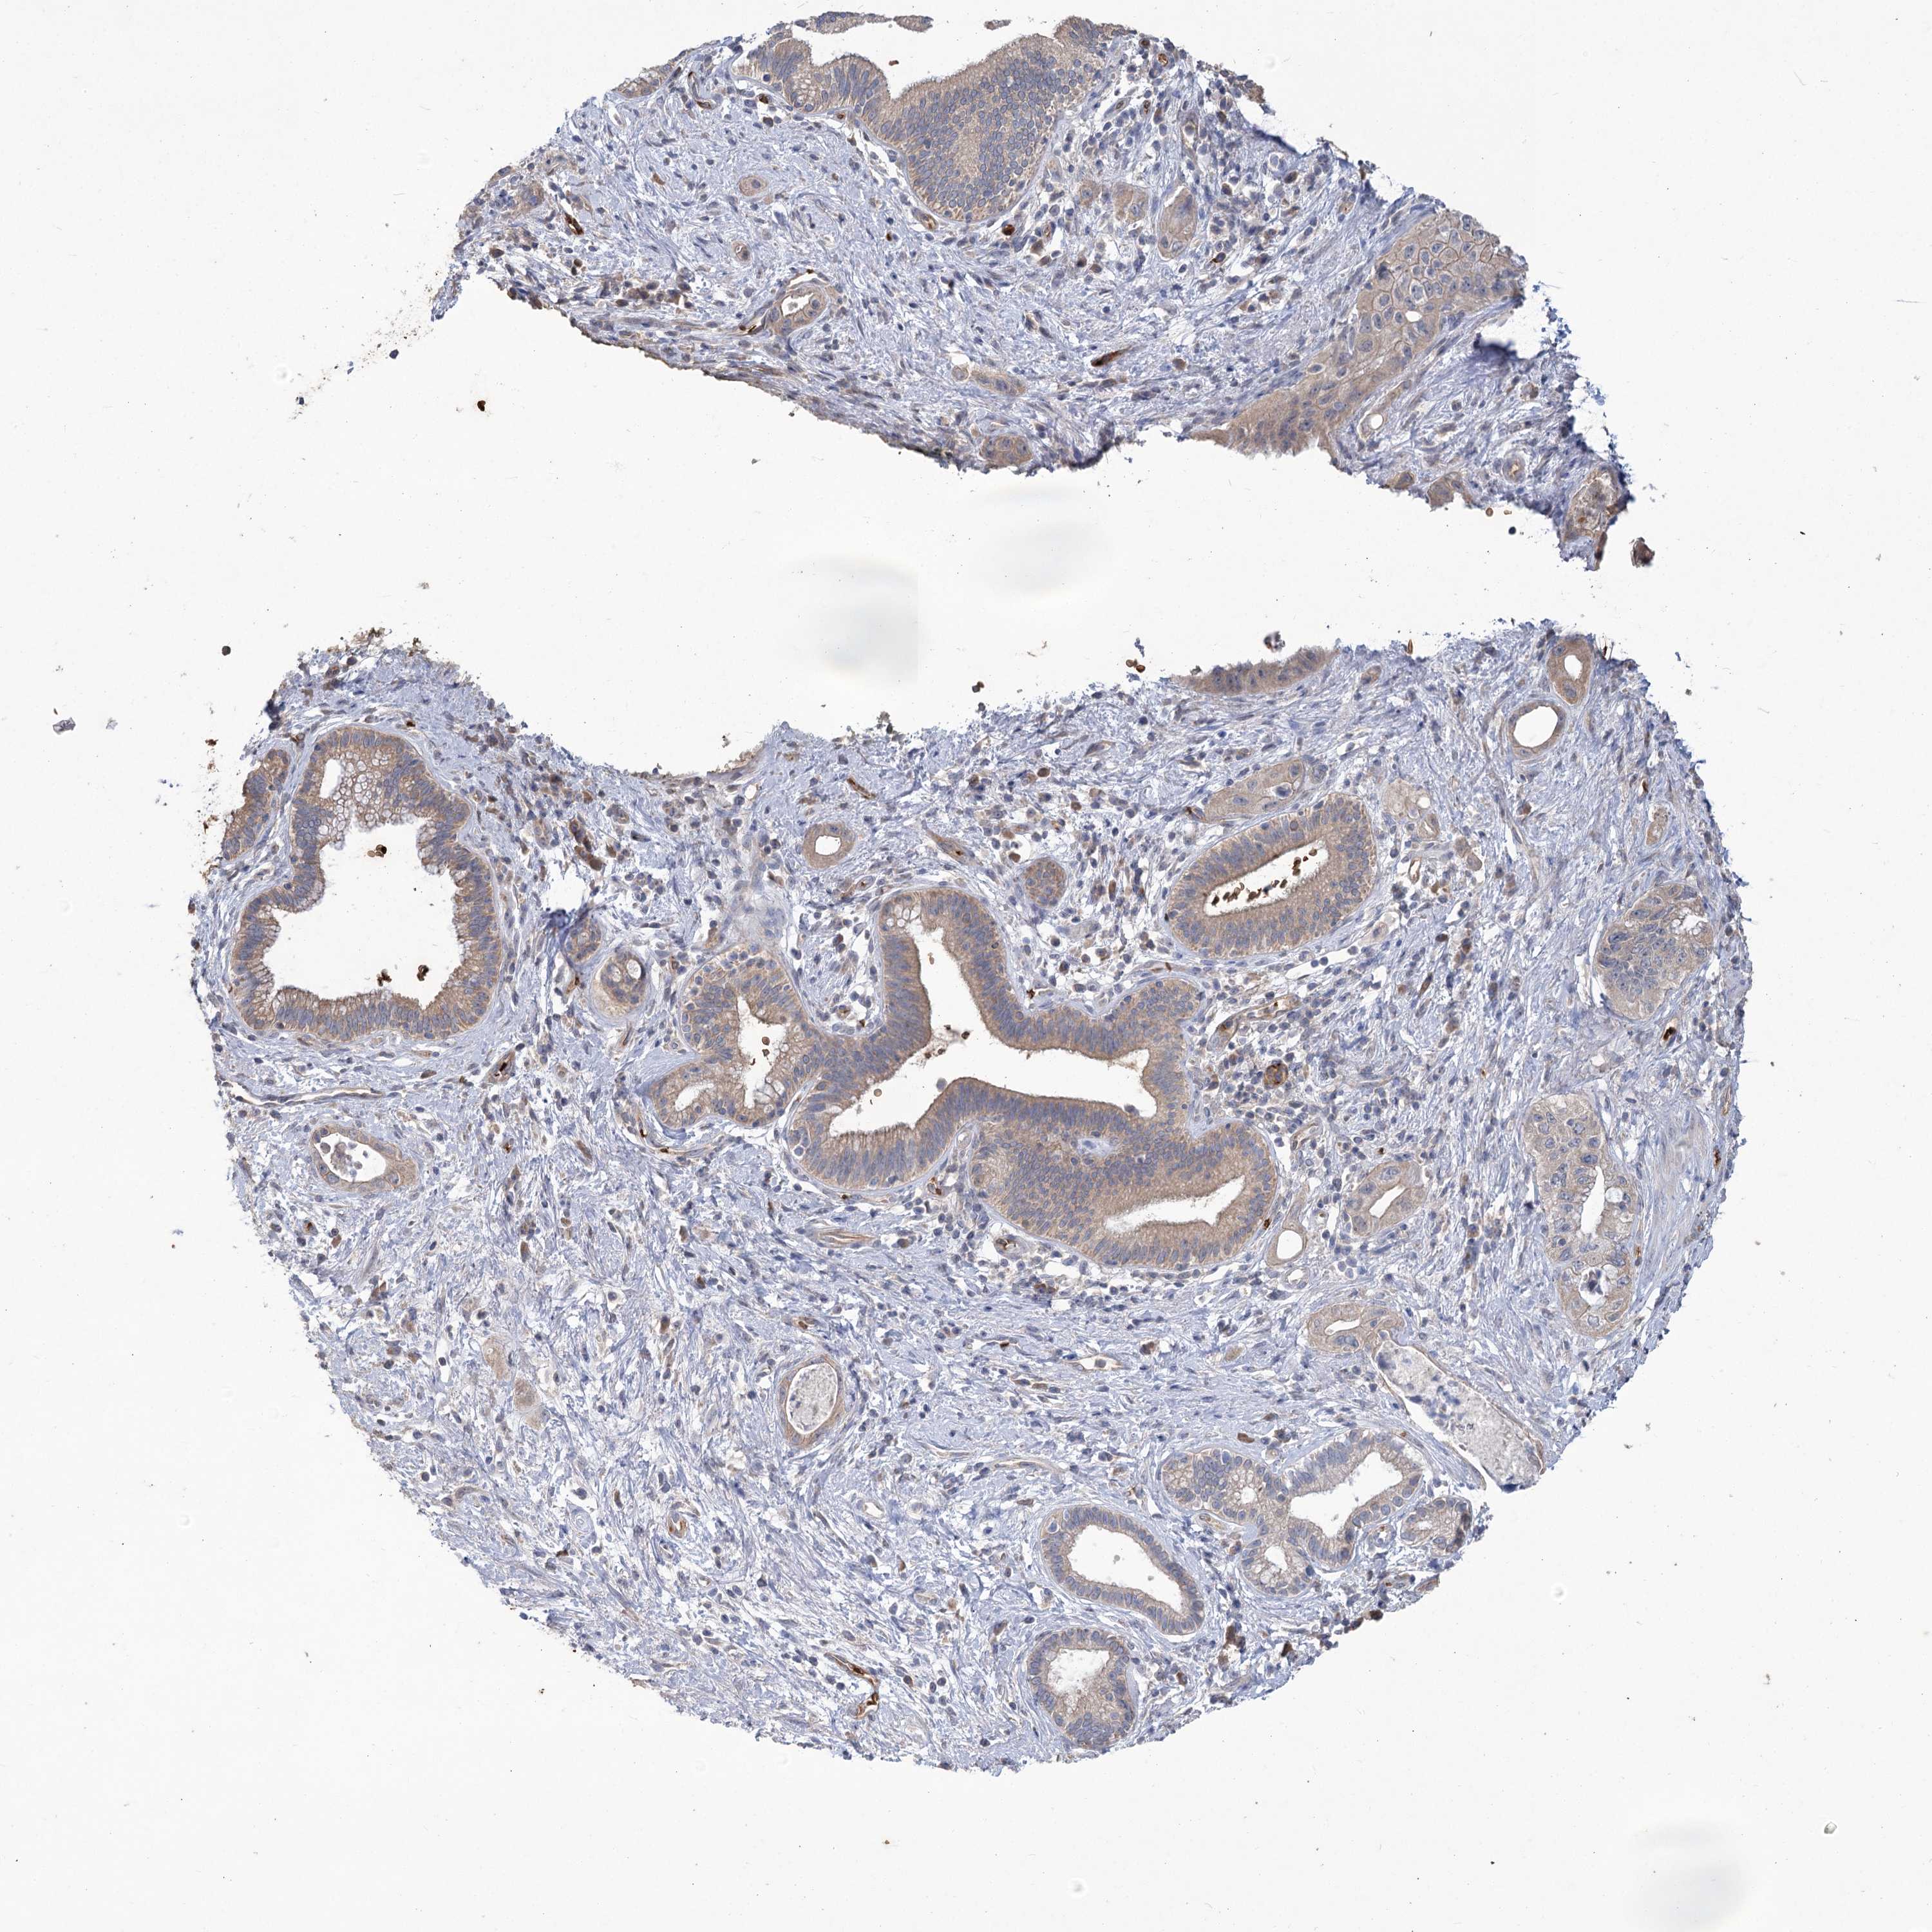

PANCREATIC CANCER - Protein expressioni

A mouse-over function shows sample information and annotation data. Click on an image to view it in a full screen mode. Samples can be filtered based on level of antibody staining by selecting one or several of the following categories: high, medium, low and not detected. The assay and annotation is described here.

Note that samples used for immunohistochemistry by the Human Protein Atlas do not correspond to samples in the TCGA dataset.

Antibody stainingi

Antibody staining in the annotated cell types in the current human tissue is reported as not detected, low, medium, or high, based on conventional immunohistochemistry profiling in selected tissues. This score is based on the combination of the staining intensity and fraction of stained cells.

Each image is clickable and will lead to virtual microscopy that enables deeper exploration of all samples and also displays staining intensity scores, fraction scores and subcellular localization as well as patient and tissue information for each sample.

Antibody HPA043780

Antibody CAB032534

Staining

High

Medium

Low

Not detected

Intensity

Strong

Moderate

Weak

Negative

Quantity

>75%

75%-25%

<25%

None

Location

Nuclear

Cytoplasmic/membranous

Cytoplasmic/membranous,nuclear

Adenocarcinoma, NOS